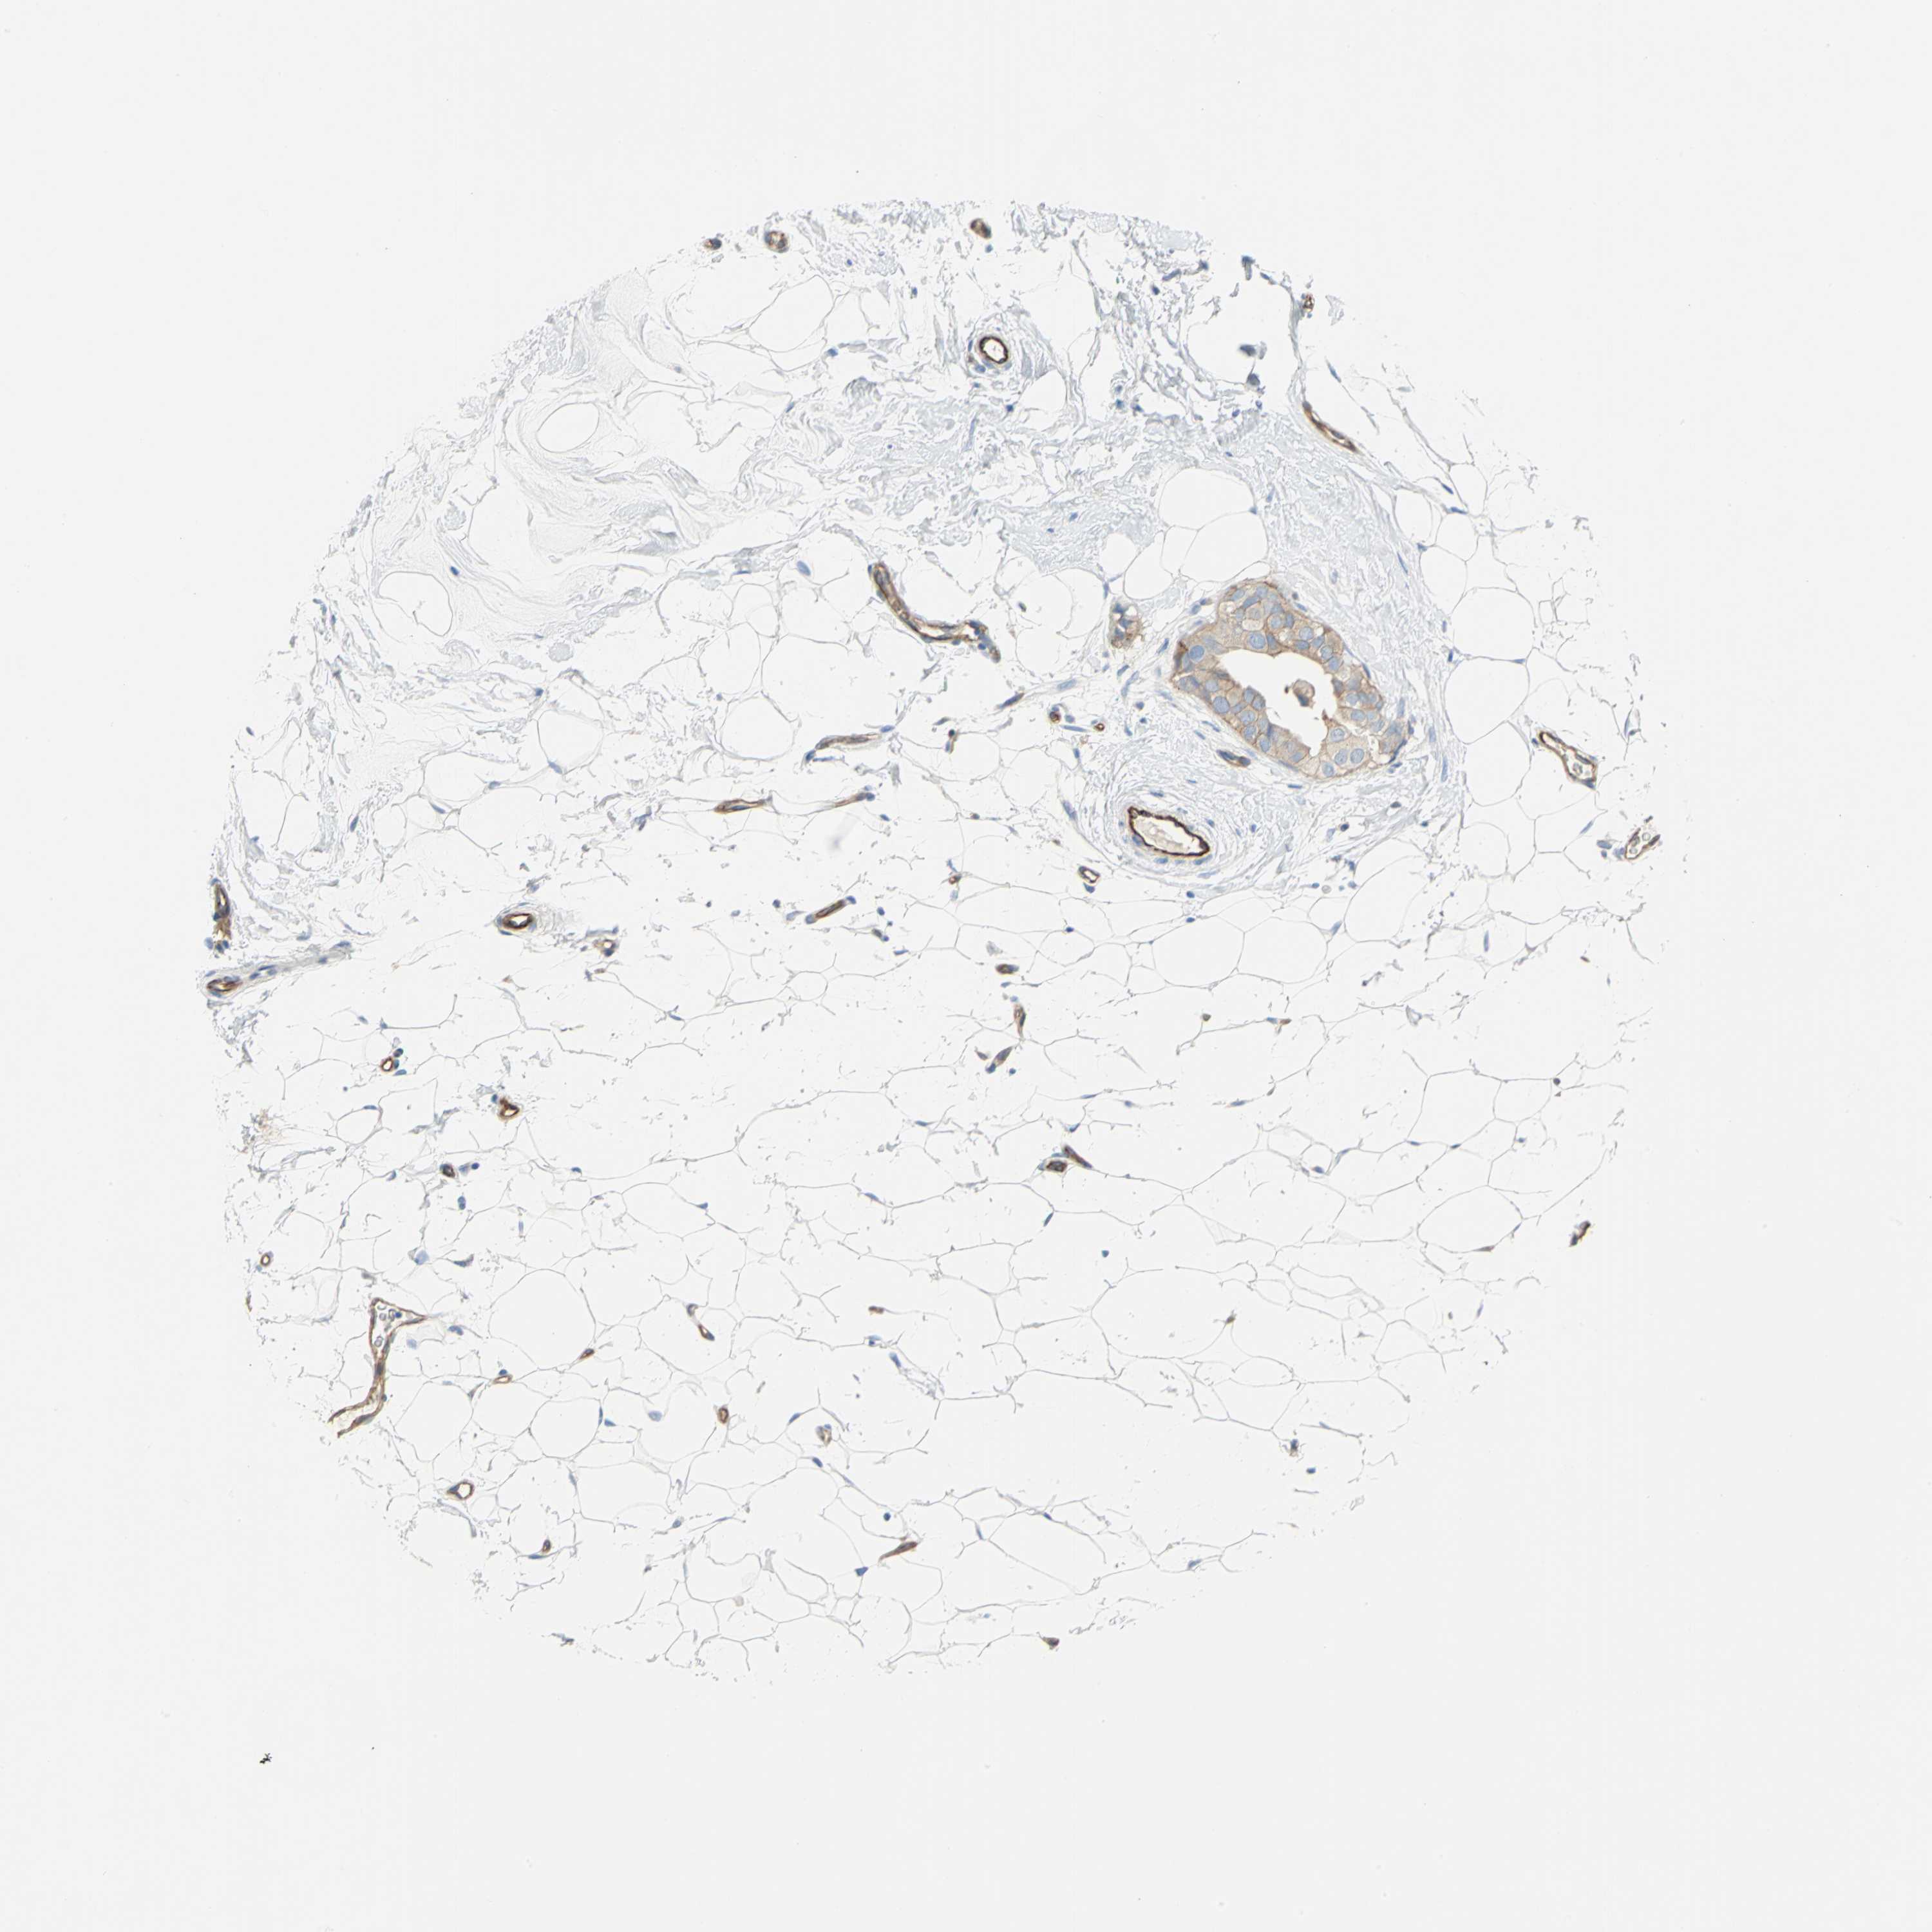

BRCA TCGA BRCA VALIDATION PROTEIN EXPRESSION